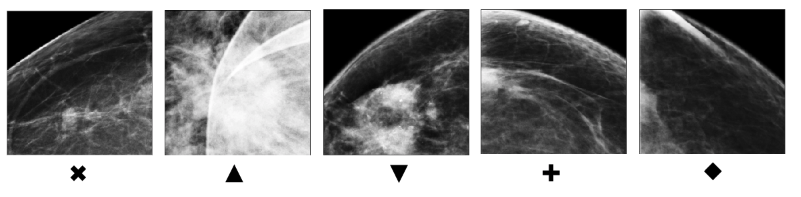

Refer to caption

Figure 1: Examples of synthesized and removed lesions by the proposed GAN architecture. Each pair of images represents a real image (left) and the synthetic counterpart (right). Each row represents a different synthesis task. Zooming is encouraged for viewing the synthesized calcifications (row 2).